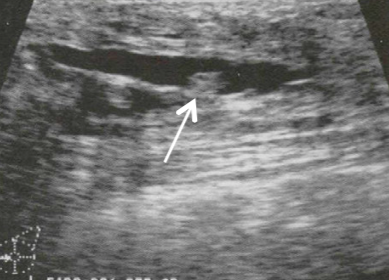

A woman presents with bloody nipple discharge, there is no palpable mass. US is performed

Intraductal papilloma